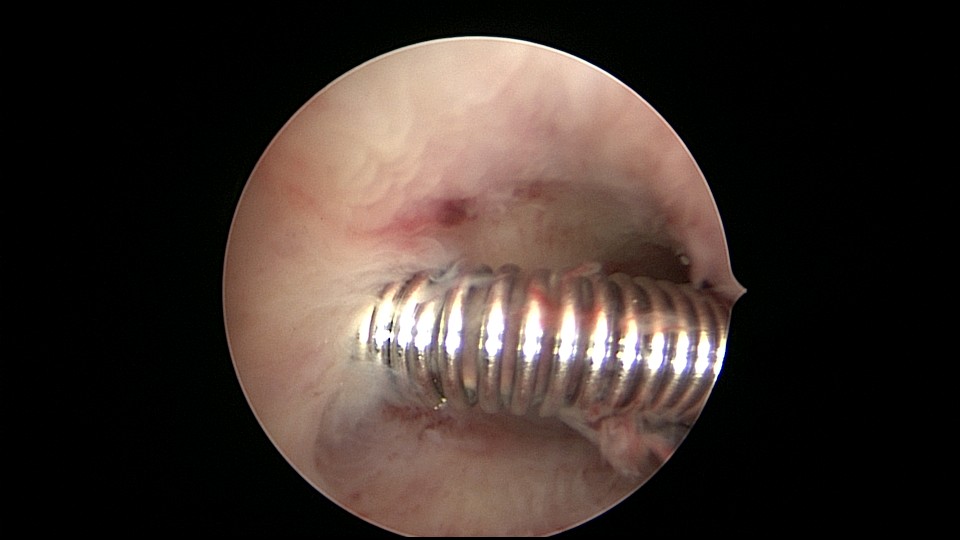

患者51岁,G4P3,顺产3次,闭经半年,外院B超提示有2个环。反复追问病史,还原宫内双环情况,24年前最后一次妊娠可能为带环受孕,行人流术,环未取出(医生和病人不知道有环),随即再次放环一枚。宫腔镜见母体乐环位置下移,纵臂卡在宫颈管内,宫腔镜难以进入宫腔,异物钳先取出母体乐。宫腔内见另一O型环,与右侧宫壁广泛嵌顿,异物钳、取环钩配合中弯钳拉出节育环,环完整,扭曲变形,宫壁见节育环割裂痕迹,宫腔无其他异常。